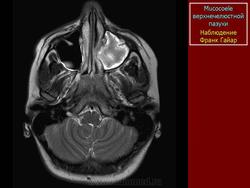

Мукоцеле

Приложения:

1.mu_.slayd364.jpg2.mu_.slayd365.jpg3.mu_.slayd366.jpg